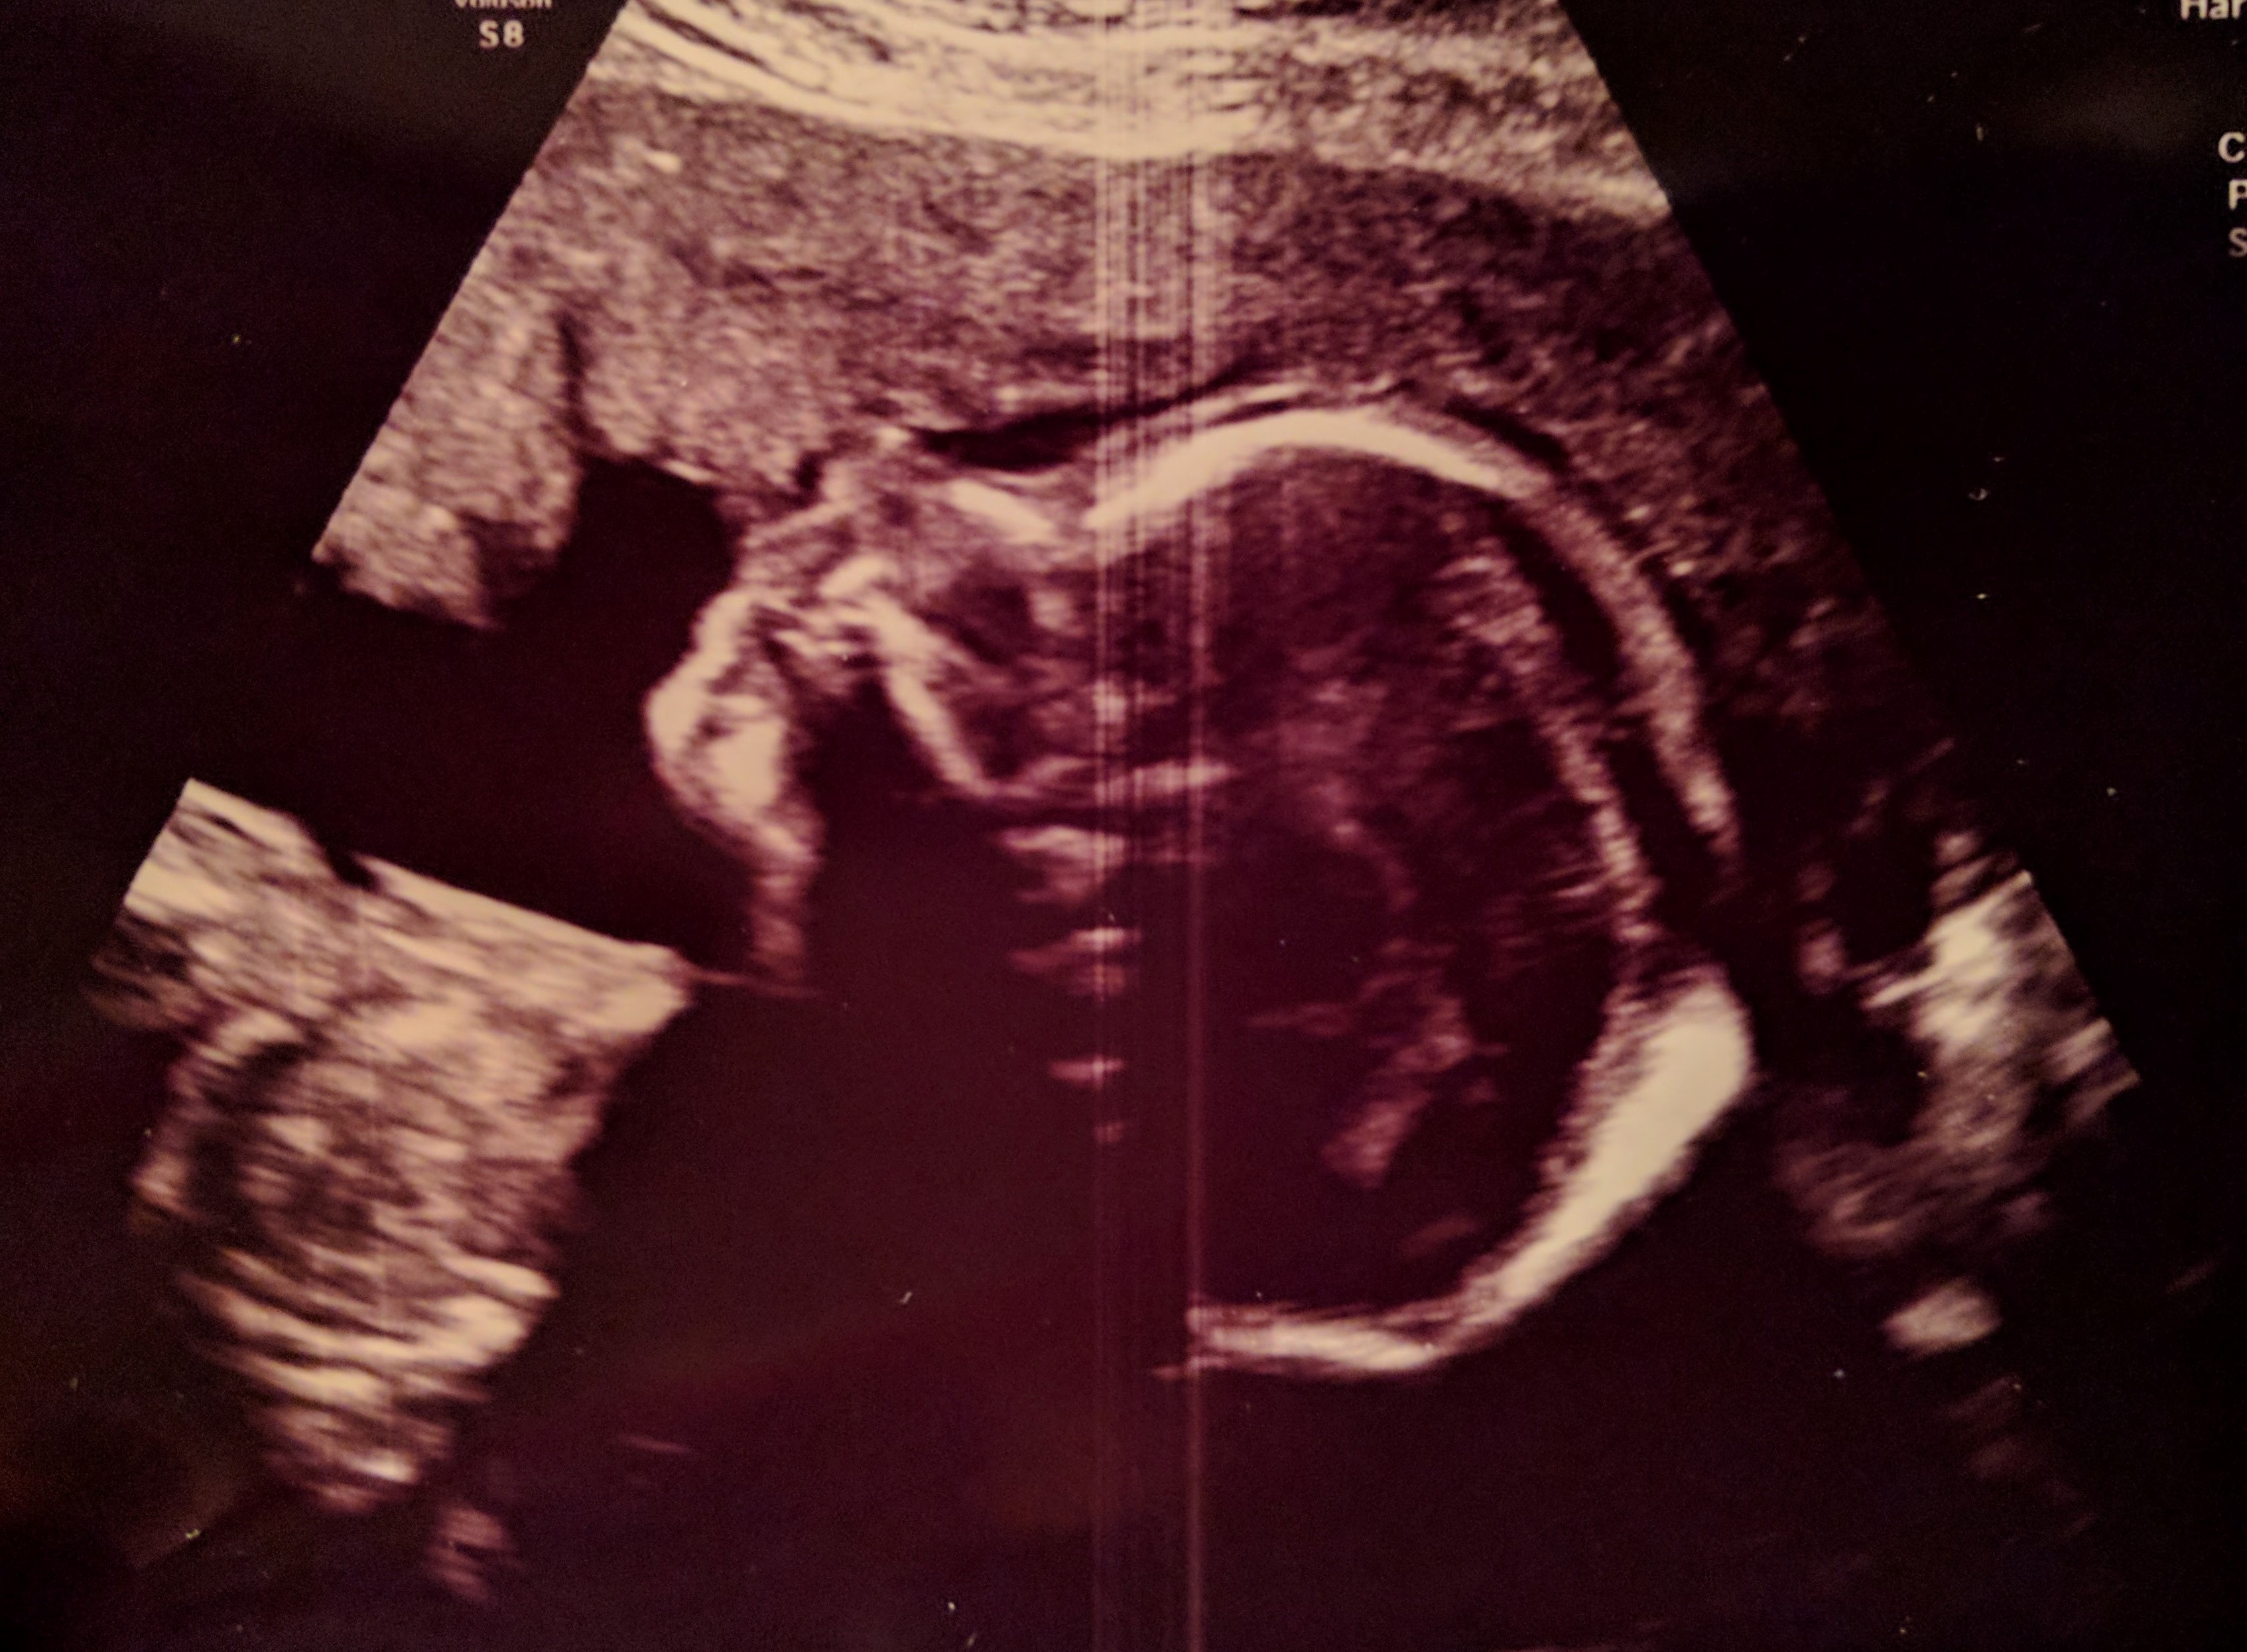

Ich sitze hier und schaue auf meinen schon sehr runden Bauch, sehe die kleinen Beulen, die hier und da kurz zu sehen sind und dann wieder verschwinden. Nie wird es aufhören, mich zu faszinieren, dass da unter dieser dünnen (naja, mitteldünnen 😉 ) Schicht aus Haut, Fett, Muskeln und Faszien ein richtiger kleiner Mensch wohnt und wächst. Mein kleines Mädchen!

Jetzt ist alles anders. Die Schwangerschaft ist schon sehr weit fortgeschritten und ich freue mich schon so darauf, meine Kleine bald endlich im Arm zu halten! Die meisten Vorbereitungen sind getroffen, unser Mädchen hat mittlerweile einen Namen und ist schon sehr präsent in unserem Alltag. Und unser Sohn hat in den letzten Monaten eine enorme Entwicklung durchgemacht. Mittlerweile lässt er sich liebend gerne von seinem Papa ins Bett bringen und schläft viele Nächte durch. Er fremdelt nicht mehr so stark und hat angefangen, zu sprechen. Es fühlt sich für mich so an, als sei auch er bereit für ein neues Familienmitglied und wir reden viel mit ihm darüber. Natürlich kann er das noch nicht so richtig verstehen, was da auf ihn und uns zukommt. Sicher wird es anfangs schwierig für ihn werden, wenn unsere Aufmerksamkeit nicht mehr ungeteilt ihm gelten kann. Aber ich habe das Gefühl, dass unsere Familienbindung jetzt so stark ist, dass wir alle miteinander das gut schaffen und davon profitieren werden. In unseren Herzen ist genug Platz für einen neuen Menschen und wir freuen uns riesig auf dieses Abenteuer.